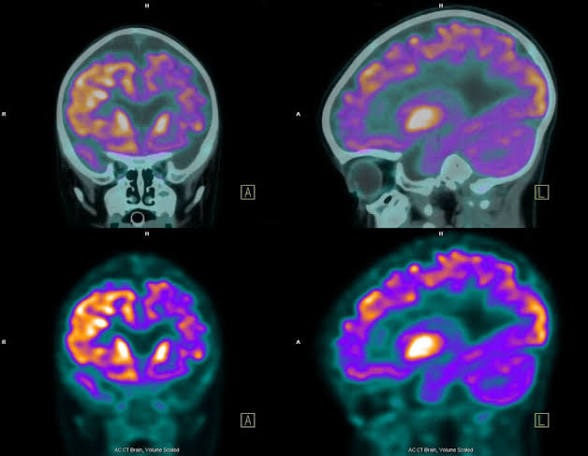

Why do so many Advanced Melanoma patients and up with brain metastases?